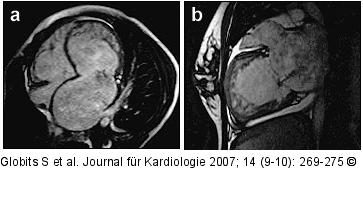

Abbildung 3a-b: Gradientenechosequenz Gradientenechosequenz in (a) axialer und (b) parasagittaler Schichtführung: non-compaction CMP, die in der Echokardiographie als apikale Hypertrophie imponiert. |

Gradientenechosequenz in (a) axialer und (b) parasagittaler Schichtführung: non-compaction CMP, die in der Echokardiographie als apikale Hypertrophie imponiert. |